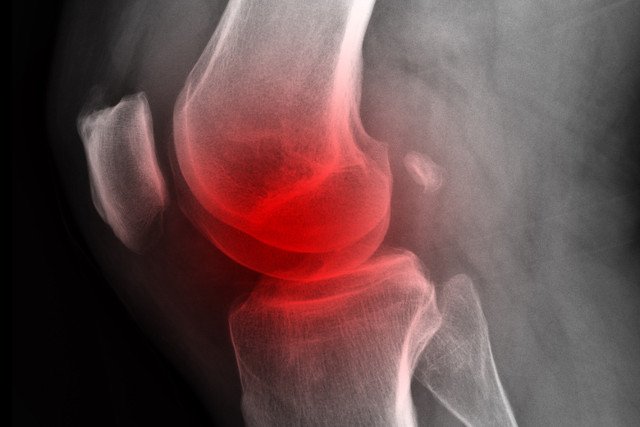

Niepokojące są także bóle kręgosłupa. Paradoksalnie to, że często stosowane leki przeciwbólowe przynoszą ulgę, powinno niepokoić, bo wskazuje to na podłoże zapalne. Powolne narastanie dolegliwości sprawia, że chorzy "przyzwyczajają się" do nich i trafiają do lekarza dopiero wtedy, gdy choroba jest zaawansowana i stawy są już poważnie uszkodzone.